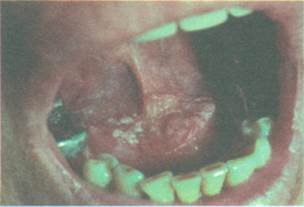

Рис. 10-2. Рак языка

Рис. 10-3. Рак слизистой оболочки щеки в области угла рта

Рис. 10-4.Рак дна полости рта на фоне лейкоплакии